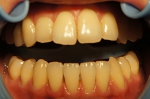

オフィスホワイトニング1日8回照射

➡

オフィスホワイトニング1日だけの症例です。

詰め物や被せ物がないのでバランス良く白くなりました。

当院のオフィスホワイトニングは薬液を使い切るまで照射回数フリーなので頑張っていただければ一日で白さを実感いただけます。